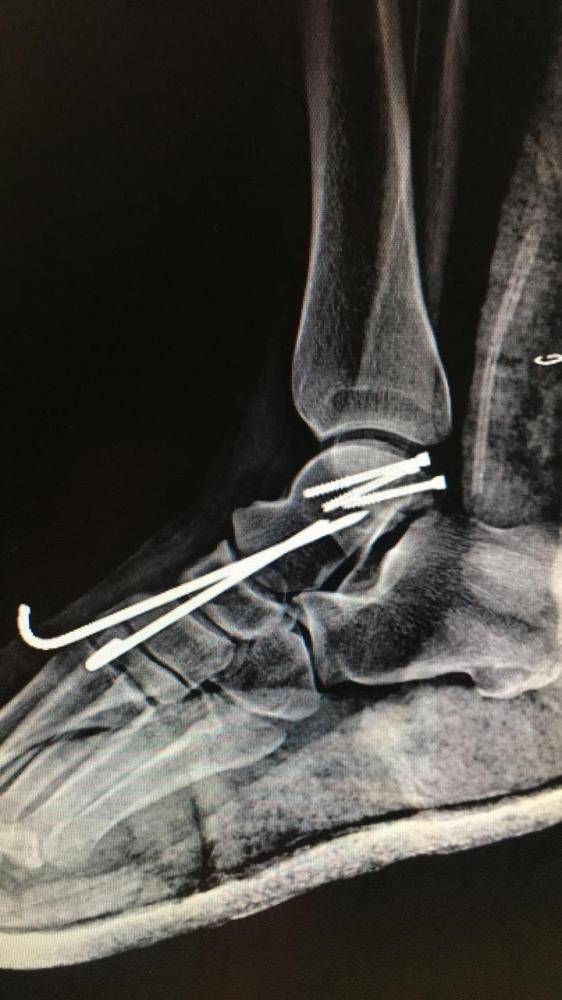

تمكن فريق طبي بمستشفى القريات العام من إنقاذ شاب سقط من «سطح منزله» نتج عنه كسر مع خلع في مفاصل القدم.

وأوضحت صحة القريات أن الفريق الطبي أجرى ردا إسعافيا للكسر مع التثبيت بأسياخ خاصة لمثل هذا النوع من الكسور، وفي مرحلة ثانية تم إجراء تثبيت للكسر ببراغي خاصة للعظام المفصلية، وتحسنت حالة المريض بعد العملية، ويخضع المريض حالياً لبرنامج علاج طبيعي وتأهيلي مكثف سيمكنه بإذن الله من استعادة الحركة.